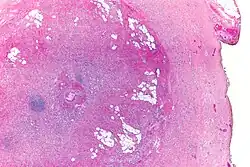

Micrograph showing a goblet cell carcinoid. H&E stain.

Micrograph of a goblet cell carcinoid. H&E stain.

GCCs are diagnosed by pathology. They have a characteristic biphasic appearance which includes (1) goblet cell-like cells, and (2) neuroendocrine-type nuclear chromatin (stippled chromatin).